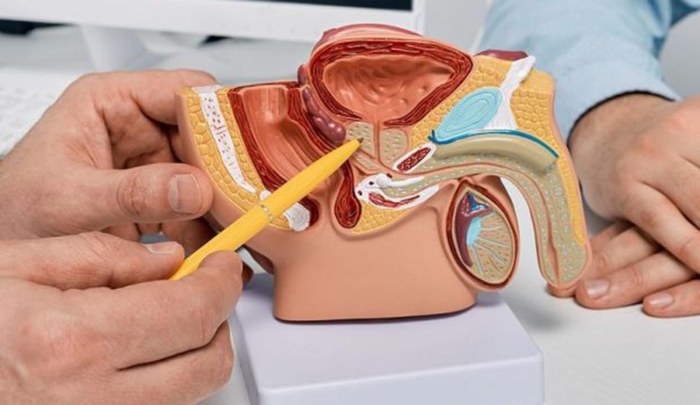

La Clínica Mayo explica que el cáncer de próstata se origina cuando las células de esta glándula masculina comienzan a multiplicarse de manera descontrolada, a continuación, te diremos las señales que no debes ignorar sobre esta enfermedad. La próstata es una glándula del tamaño de una nuez que produce parte del líquido seminal. El cáncer de próstata es uno de los más comunes entre los … Continuar leyendo Señales que no debes ignorar sobre el cáncer de próstata

El cáncer de próstata es un tipo de cáncer que se forma en la próstata, una glándula pequeña con forma de nuez que produce el líquido seminal en los hombres, a continuación, te advertimos sobre las señales que da esta enfermedad y que NO debes ignorar. El cáncer de próstata es el tumor maligno más común en hombres, por lo que es … Continuar leyendo ¿Cuáles son las señales del cáncer de próstata que NO debes ignorar?